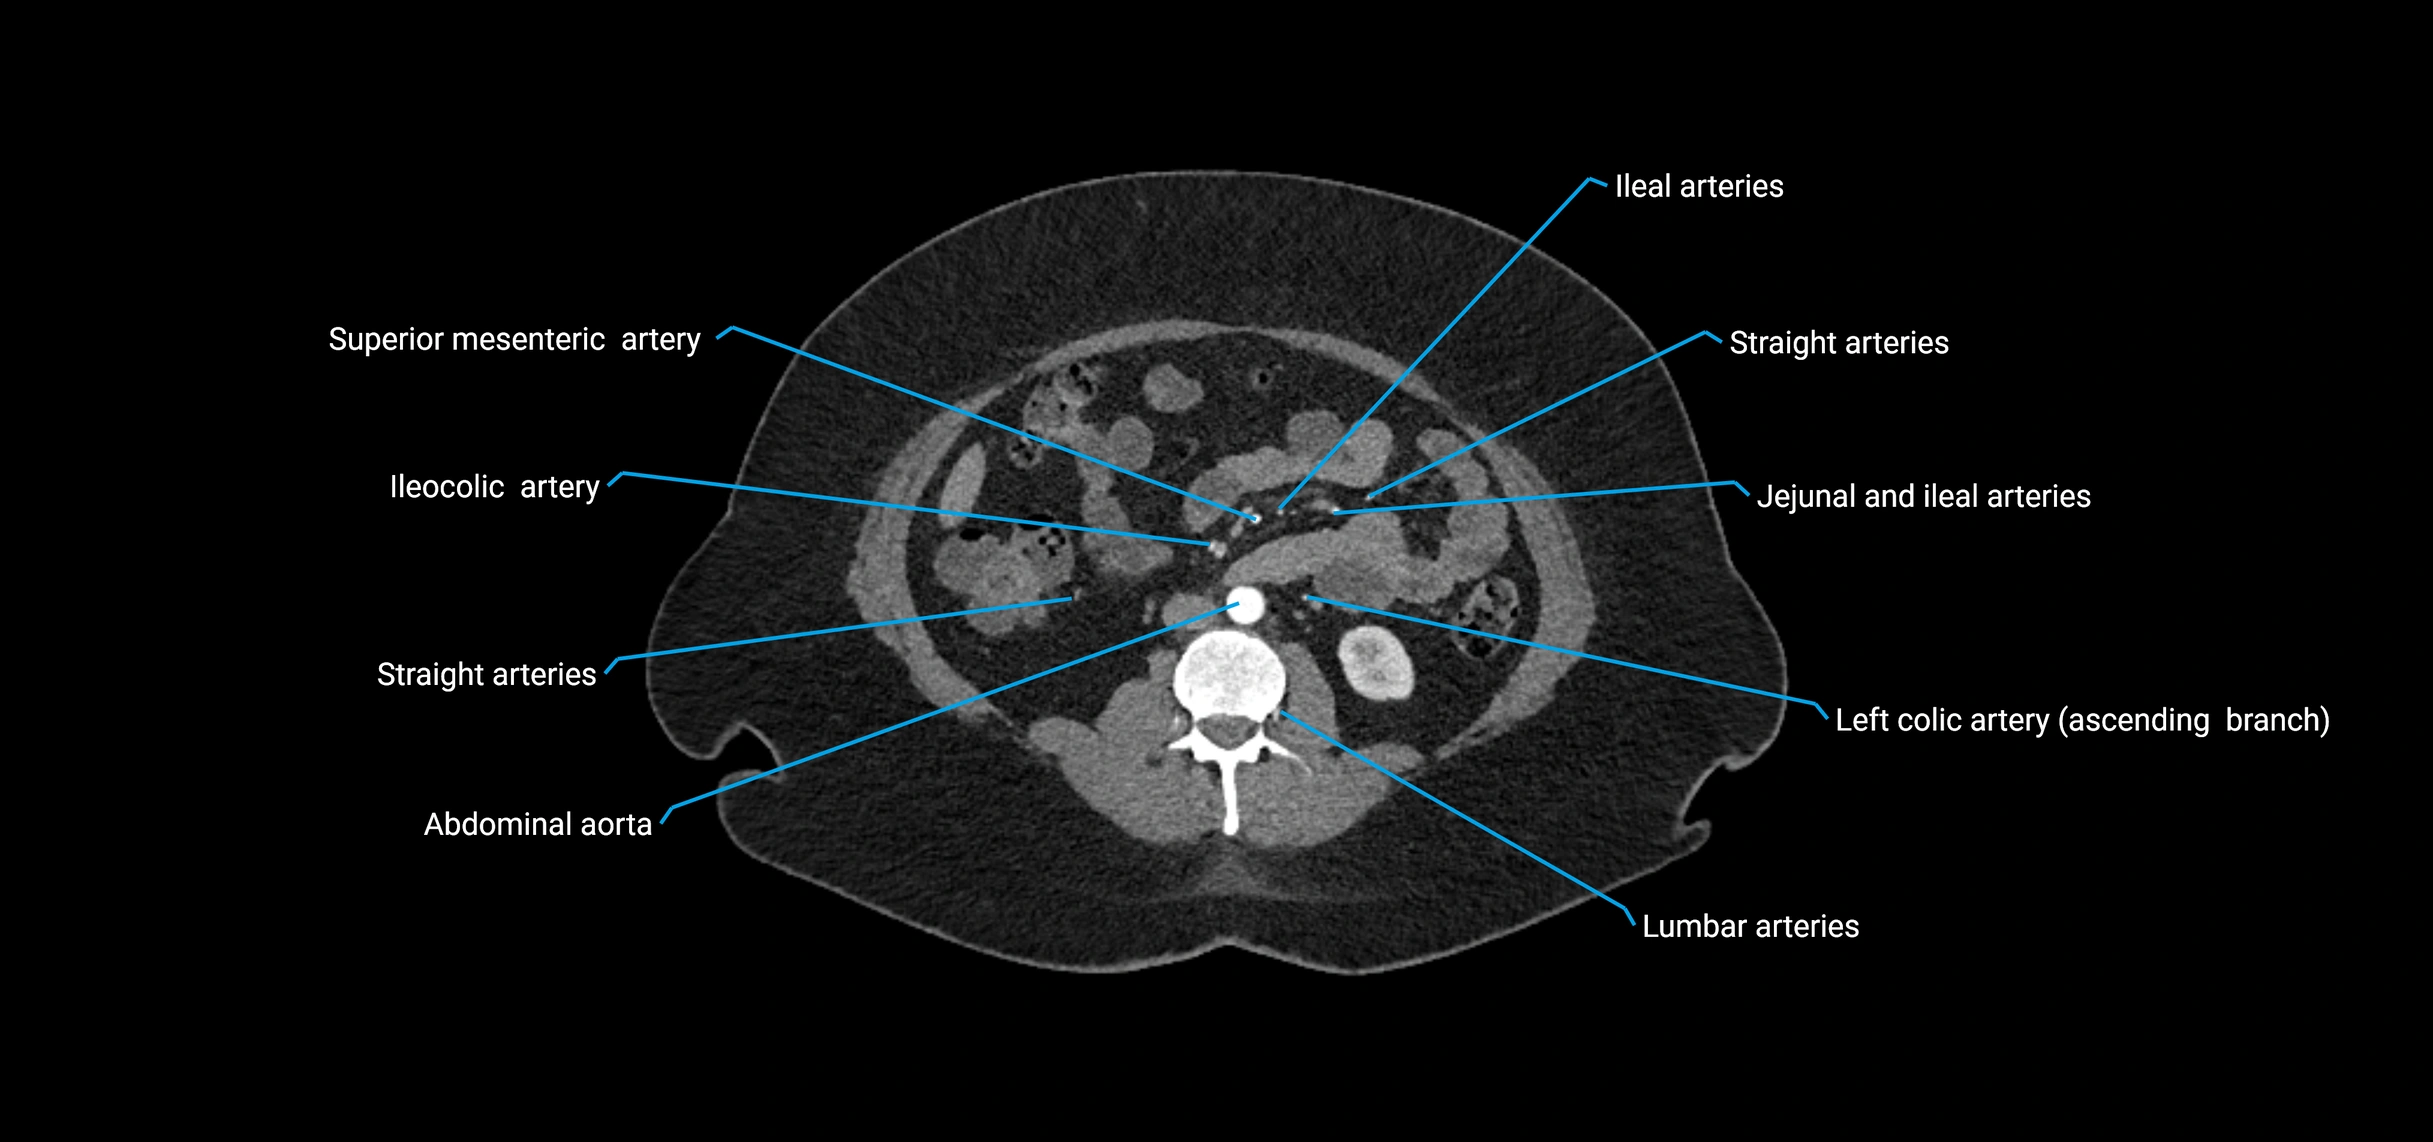

CT images

image

Contrast-enhanced CT (CTA):

• Gold standard for abdominal aortic imaging

• Provides excellent detail of lumen, wall, aneurysm, thrombus, and branch vessels

• Multiplanar and 3D reconstructions help in aneurysm measurement, stent graft planning, and dissection evaluation